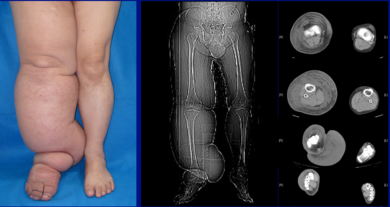

| Lower extremity lymphedema | |

The most common manifestation of lymphedema is soft tissue swelling, edema. As the disorder progresses, worsening edema and skin changes including discoloration, verrucous (wart-like) hyperplasia, hyperkeratosis, papillomatosis, dermal thickening, and ulcers may be seen. Additionally, there is increased risk of infection of the skin, known as Erysipelas.

Diagnosis is generally based on signs and symptoms, with testing used to rule out other potential causes.[2] An accurate diagnosis and staging may help with management.[2] A swollen limb can result from different conditions that require different treatments. Diagnosis of lymphedema is currently based on history, physical exam, and limb measurements. Imaging studies such as lymphoscintigraphy and indocyanine green lymphography are only required when surgery is being considered.[2] However, the ideal method for lymphedema staging to guide the most appropriate treatment is controversial because of several different proposed protocols.[29][30] Lymphedema can occur in both the upper and lower extremities, and in some cases, the head and neck. Assessment of the extremities first begins with a visual inspection. Color, presence of hair, visible veins, size and any sores or ulcerations are noted. Lack of hair may indicate an arterial circulation problem.[31] Given swelling, the extremities' circumference is measured for reference as time continues. In early stages of lymphedema, elevating the limb may reduce or eliminate the swelling. Palpation of the wrist or ankle can determine the degree of swelling; assessment includes a check of the pulses. The axillary or inguinal nodes may be enlarged due to the swelling. Enlargement of the nodes lasting more than three weeks may indicate infection or other illnesses such as sequela from breast cancer surgery requiring further medical attention.[31]

Chronic venous stasis changes can mimic early lymphedema, but the changes in venous stasis are more often bilateral and symmetric. Lipedema can also mimic lymphedema, however lipedema characteristically spares the feet beginning abruptly at the medial malleoli (ankle level).[2] As a part of the initial work-up before diagnosing lymphedema, it may be necessary to exclude other potential causes of lower extremity swelling such as kidney failure, hypoalbuminemia, congestive heart-failure, protein-losing nephropathy, pulmonary hypertension, obesity, pregnancy and drug-induced edema.[citation needed]

- Stage 3: Swelling is irreversible and usually the limb(s) or affected area becomes increasingly large. The tissue is hard (fibrotic) and unresponsive; some patients consider undergoing reconstructive surgery, called "debulking". This remains controversial, however, since the risks may outweigh the benefits and the further damage done to the lymphatic system may in fact make the lymphedema worse.

- Stage 4: The size and circumference of the affected limb(s) become noticeably large. Bumps, lumps, or protrusions (also called knobs) on the skin begin to appear.

- Stage 5: The affected limb(s) become grossly large; one or more deep skin folds is prevalent among patients in this stage.

- Grade 4 (gigantic edema): In this stage of lymphedema, the affected extremities are huge, due to almost complete blockage of the lymph channels.